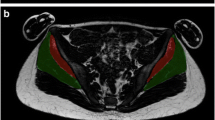

Carnosine spectra were acquired in phantoms (5, 10, and 15 mM) as well as in the right gastrocnemius medialis (GM) and right vastus lateralis (VLM) muscles of young team sports athletes, using volume (VC) and surface (SC) coils on a 3 T scanner, with the same receiver gain. Water spectra were used as internal reference for the absolute quantification of carnosine.

Phantom’s experiments showed a maximum error of 7%, highlighting the validity of the measurements in the study setup. The carnosine concentrations (mmol/kg ww, mean ± SD) measured in the GM were 6.8 ± 2.2 with the VC (CcarVC) and 10.2 ± 3.0 with the SC (CcarSC) (P = 0.013; n = 9). Therefore, a correction was applied to these measurements (CcarVC = 0.6582*CcarSC), to make coils performance comparable (6.8 ± 2.2 for VC and 6.7 ± 2.0 for SC, P = 0.97). After that, only the SC was used to quantify carnosine in the VLM, where a concentration of 5.4 ± 1.5 (n = 30) was found, with significant differences between men (6.2 ± 1.3; n = 15) and women (4.6 ± 1.2; n = 15). The error in quantitation was 5.3–5.5% with both coils.

The method using the SC and water as internal reference can be used to quantify carnosine in voluminous muscles and regions of the body in humans, where the VC is not suitable, such as the VLM.